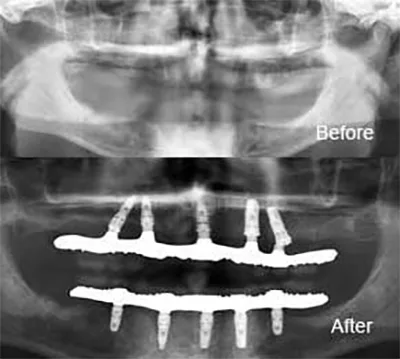

การฝังรากแบบนี้เป็นวิธีที่ทำกันโดยทั่วไป สามารถทำได้เกือบทุกกรณี สามารถฝังรากฟันเทียมชนิดนี้เพื่อทดแทนฟันที่สูญเสียไปเพียงซี่เดียว หลายซี่ หรืออาจจะทั้งปาก

โดยปกติแล้วการฝังรากฟันเทียมแบบทั่วไปนั้นแบ่งออกเป็น 2 ขั้นตอน ระยะห่างแต่ละขั้นตอนนั้นห่างกันประมาณ 2-6 เดือน

การฝังรากฟันเทียมแบบทั่วไปสามารถทำได้ในสภาพกระดูกขากรรไกรของคนไข้ส่วนใหญ่ แต่หากในบางกรณีที่คนไข้กระขากรรไกรมีความบางกว่าปกติ หรือมีการสูญเสียกระดูกบริเวณที่จะทำหารฝังรากฟันเทียม ทันตแพทย์เฉพาะทางอาจพิจารณาให้ปลูกกระดูกก่อนรับการฝังรากฟันเทียม เพื่อให้กระดูกบริเวณนั้นมีความหนา และแข็งแรงพอรองรับการฝังรากฟันเทียม